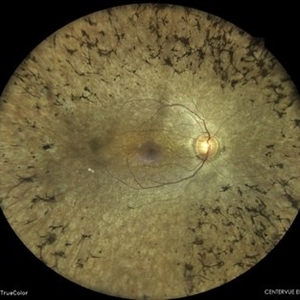

RETINITIS PIGMENTOSA

COLOUR FUNDUS PHOTOGRAPH OF A 30 YEAR OLD MALE WITH RETINITIS PIGMENTOSA

Photographer: Dr. Akansha Sharma-Retina Foundation, Ahmedabad

Condition/keywords: retinitis pigmentosa (RP) dystrophy, RP variant